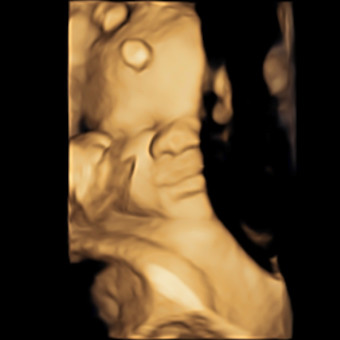

Angela's Baby Registry

Never would’ve thought I’d be starting all over 😅 another little boy on the way, anything is greatly appreciated ❤️